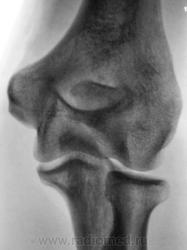

Травма.     Пациент направлен на рентгенографию локтевого сустава.

Перелом локтевого отростка - на операцию

А как Вы считаете коллега, как травматолог, косые проекции, в данном конкретном случае, "принесли" какую-то дополнительную информацию?

Если рассуждать с точки зрения только диагностики перелома - нет, так как перелом хорошо виден и на стандартных проекциях. С точки зрения дальнейшей лечебной тактики - да. Так как косые проекции выявили безусловную необходимость оперативного лечения.